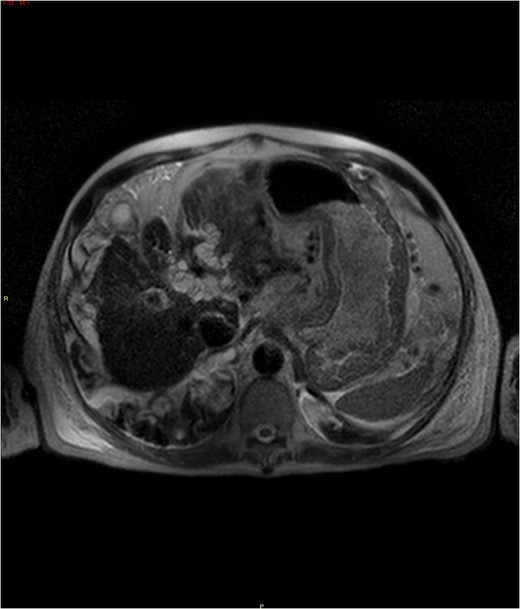

Magnetic resonance imaging (MRI) of the abdomen revealed increased T2 signal intensity within the bile ducts and significant dilation predominantly of the left biliary ductal system, with a lesser dilation of the right-sided bile ducts (Fig. 1). This was a new finding as compared to imaging from 6 months prior to hospitalization. There were no detectable hepatic or pancreatic head masses. The cholestatic pattern of liver enzyme abnormality and new biliary ductal dilatation in the absence of choledocholithiasis or a pancreatic head mass was concerning for CCA.

MRI abdomen demonstrating increased T2 signal intensities along the left bile ducts and to lesser extent the right bile ducts.